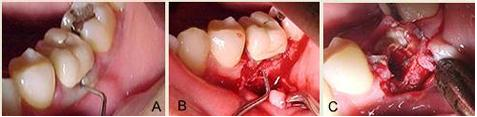

Figuras 1 a, b e c.

Figura 1a, mostra a sonda milimetrada penetrando mais de 10mm dentro da lesão na área da bifurcação.

Figura 1b, o retalho total foi realizado e rebatido, com a cureta MacCall 13-14, todo tecido de granulação foi removido, durante esse procedimento a coroa se soltou e foi removida da raiz.

Figura 1c, mostra o momento que a coroa foi removida e parte da raiz mesial, fraturada saiu junto com o núcleo, expondo todo defeito ósseo na área da bifurcação.